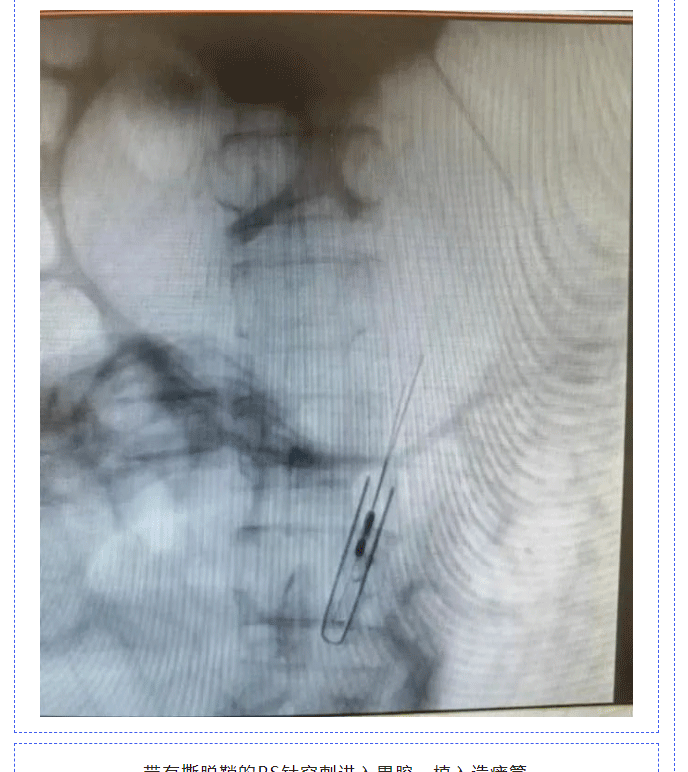

【新技术新项目】贵溪市人民医院介入血管科成功开展本地区首例经皮透视下胃造瘘术